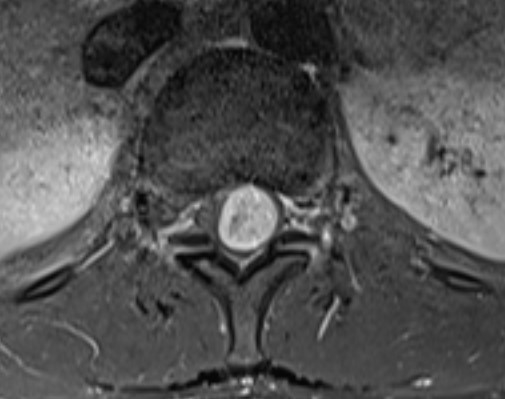

Bei der Magnetresonanztomographie, kurz MRT, handelt es sich um eine bildgebende Untersuchung, bei der die Strukturen des Beckens und der darin befindlichen Organe ohne Strahlung dargestellt werden können. Im Gegensatz zum herkömmlichem Röntgen und der Computertomographie werden bei der MRT starke Magnetfelder und Radiowellen zur Aufnahme der Bilder verwendet. Darüber hinaus ermöglicht dies sehr detaillierte, hochauflösende Bilder. Die MRT-Untersuchungen sind schmerzfrei und ungefährlich.

Die Magnetresonanztomographie überzeugt durch ihren hohen Weichteilkontrast. Damit eignet sich dieses bildgebende Verfahren ideal zur Beurteilung von Tumoren, Entzündungen und Nekrosen von Knochen, Weichteilen und Organen sowie von Schäden am Kapselbandsystem der Gelenke und inneren Gelenkverletzungen.

Der Körper wird zweidimensional Schicht für Schicht gescannt, wodurch zahlreiche Querschnittsbilder entstehen. Diese werden dann am Computer übereinander geschichtet, sodass ein dreidimensionaler Eindruck entsteht. Auch rechnerisch ist eine exakte 3D-Rekonstruktion möglich, sodass die in der MRT entstandenen Bilder anschließend aus jedem Blickwinkel betrachtet werden können. Anhand dieser MRT Bilder können verschiedenste Strukturen und Funktionen des Beckens und Körperinneren detailliert beurteilt werden.

Knochen, Gelenke, Muskeln und Organe des Beckens können mittels MRT ohne Strahlenbelastung dargestellt werden. Auf diese Weise können verschiedenste Veränderungen oder Verletzungen erkannt und beurteilt werden.

Dementsprechend kann die MRT bei verschiedenen Verdachtsdiagnosen die bevorzugte bildgebende Untersuchung sein:

• Einstufung gutartiger oder bösartiger Tumore

• Entzündliche Darmerkrankungen (z. B. Morbus Crohn, Colitis ulcerosa)

• gynäkologische Erkrankungen (z. B. Endometriose, Ovorialkarzonom, Zervixkarzinom)

• Ursache für Stuhl- und Harninkontinenz

• Prostataerkrankungen (z. B. gutartige Prostatahyperplasie, Prostatakrebs)

• Diagnose von Darmfisteln

• Leistenbruch

• Funktionsstörung des Beckenbodens

Aufgrund der engen anatomischen Verhältnisse ist eine engmaschige Überwachung insbesondere bei bösartigen Erkrankungen im Beckenbereich wie Tumore der Gebärmutter, der Eierstöcke, der Prostata und des Mastdarms unerlässlich. So können Ausmaß und mögliche Größenzuwächse frühzeitig abgeschätzt und erkannt werden. Die MRT ermöglicht es, ohne ionisierende und schädliche Strahlung einen Krankheitsverlauf stätig zu begleiten.

Auch vor möglichen chirurgischen Eingriffen kann eine MRT des Beckens notwendig sein, um vorab die genauen Umgebungsbedingungen zu kennen. Aufgrund des hohen Weichteilkontrasts ist bei Untersuchungen des Beckens meist die MRT Becken die Methode der Wahl, da sich so die Organe und umliegenden Strukturen optimal voneinander unterscheiden lassen.